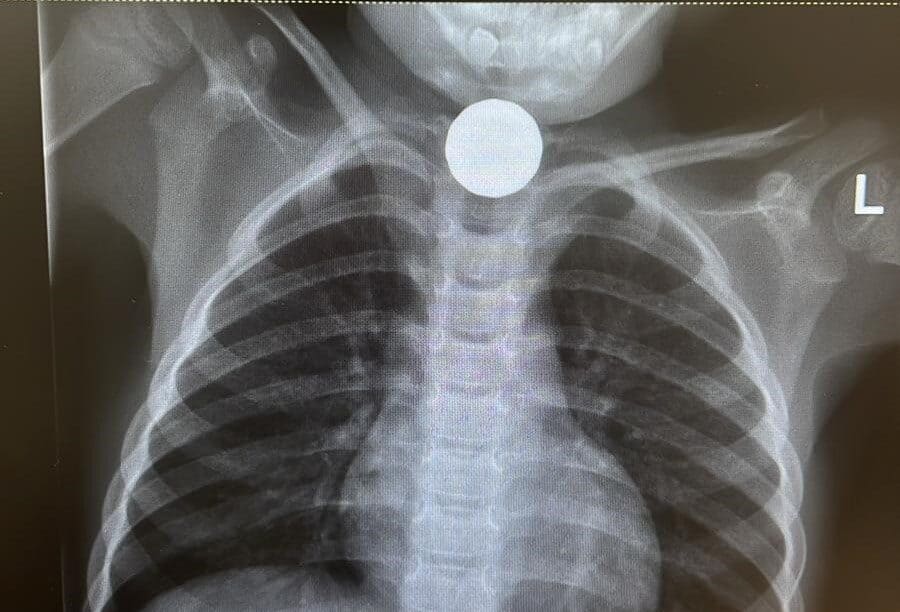

הרופא שבדק את הילד במלר"ד מאוחדת בירושלים, הבחין שמצבו לא טוב, העביר אותו לצילום רנטגן דחוף וזיהה כי המטבע קרוב לקנה הנשימה. כך ניצלו חייו

את פניו קיבל ד"ר עודה עלאם, רופא במערך הרפואה הדחופה במאוחדת שמספר: "הבחנתי מיד שמצבו לא טוב והעברתי אותו במיידי לצילום רנטגן. בצילום ראינו באופן ברור כי הוא בלע מטבע של חמישה שקלים, אשר נתקע קרוב מאוד לקנה הנשימה עם חשש ממשי לחנק. ביקשתי למנוע כל תזוזה של הילד שעלולה להביא לחסימת נתיבי האוויר שלו עד לפינוי לבית החולים".